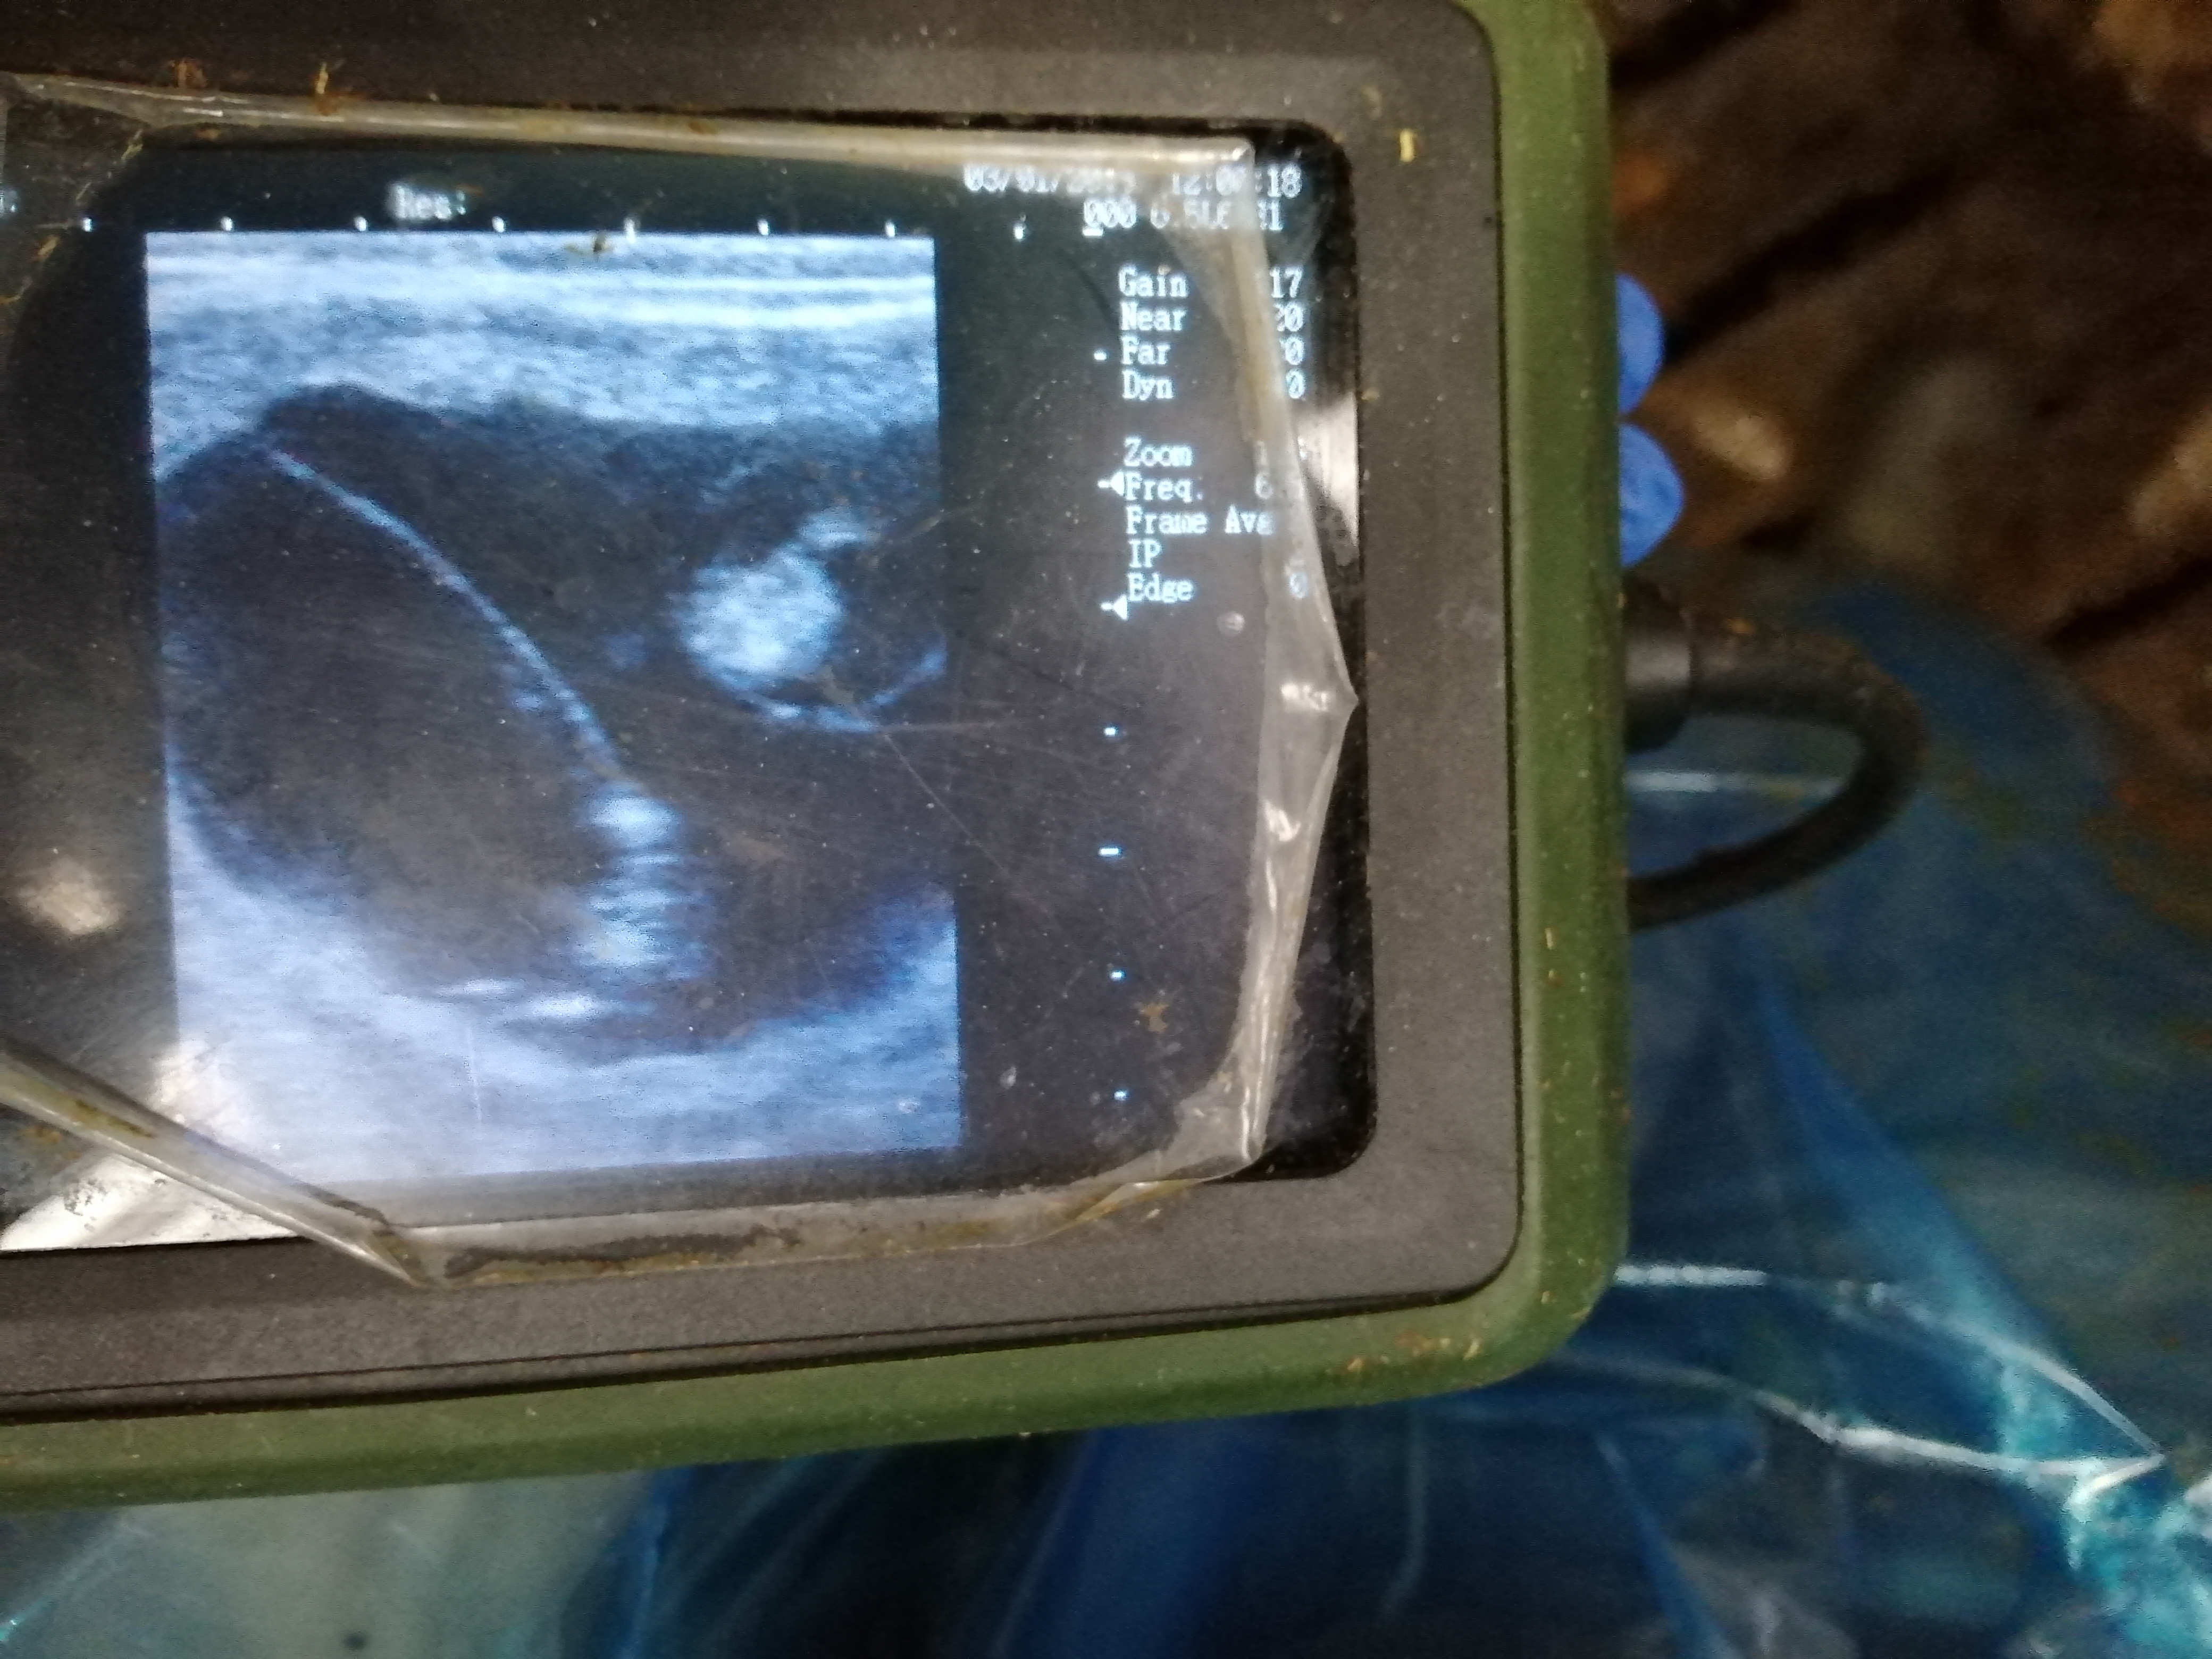

Maandag was het terug de eerste maandag van de maand en dus was veearts Bart van de partij voor vruchtbaarheidsbegeleiding en drachtcontrole. Bij het controleren op dracht kwamen we bij koe Britney een opvallend beeld tegen. De scan toonde twee vruchtjes! Het gaat hier zo goed als zeker om een tweeling!

Koe Britney zit wel nog in een vroeg stadium: ze is nog maar 45 dagen drachtig. Het is dus nog afwachten hoe de dracht – de zwangerschap dus – verder zal verlopen. Het is de eerste keer dat ik een tweeling te zien krijg op de scan, het is dan ook nog maar een paar maanden dat we dit regelmatig doen. Ik vind het telkens spannend uitkijken naar de resultaten van m’n kunstmatige inseminaties!